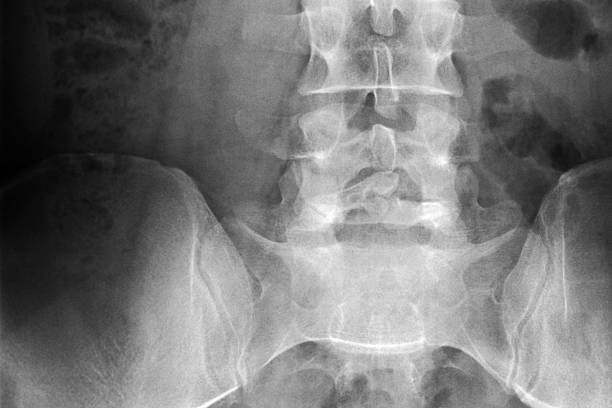

✅요추 염좌 회복기간 알아보기

사람마다 회복하는 기간은 다르겠지만 빠르게 회복을 위한 방법이 있습니다.

역시나 가장 정확한것은 의사선생님 말씀이 최고겠죠?

어떻게 해야 요추 염좌 회복기간 빠르게 단축시킬 수 있는지 확인해보세요.